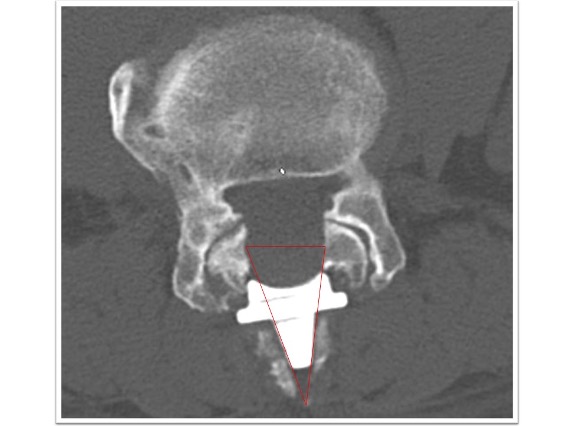

経皮的椎体形成術(BKP)

高齢患者様の圧迫骨折ではこれまで保存的治療が中心となってきましたが、長期のベッド上安静によって著しい筋力低下をきたし、歩行の再開が困難、あるいはリハビリが長期に及ぶことも少なくありません。経皮的椎体形成術(BKP)では、胸腰椎の圧迫骨折に対して骨セメントを骨折した椎体に注入することで除痛、骨折部位の安定化を図ります。

BKPは3mm程度の非常に小さな傷からの治療が可能です。痛みが続く場合、比較的早期にこの治療を行うことで患者様の日常生活への早期復帰を促します。痛みが術後から改善することで多くの患者様は翌日から術前よりも動くことが出来るようになります。手術は全身麻酔下に行われ、手術時間は通常約30分です。

経皮的椎体形成術実例(*患者様の許可を得て掲載しています)

胸椎圧迫骨折

胸椎圧迫骨折後、遷延する腰痛と骨癒合不良を認めていた椎体に対してBKPを実施しています。治療後レントゲン画像では椎体内に注入された骨セメントと椎体高が改善していることが確認できます。腰痛改善し術翌日に退院となっています。